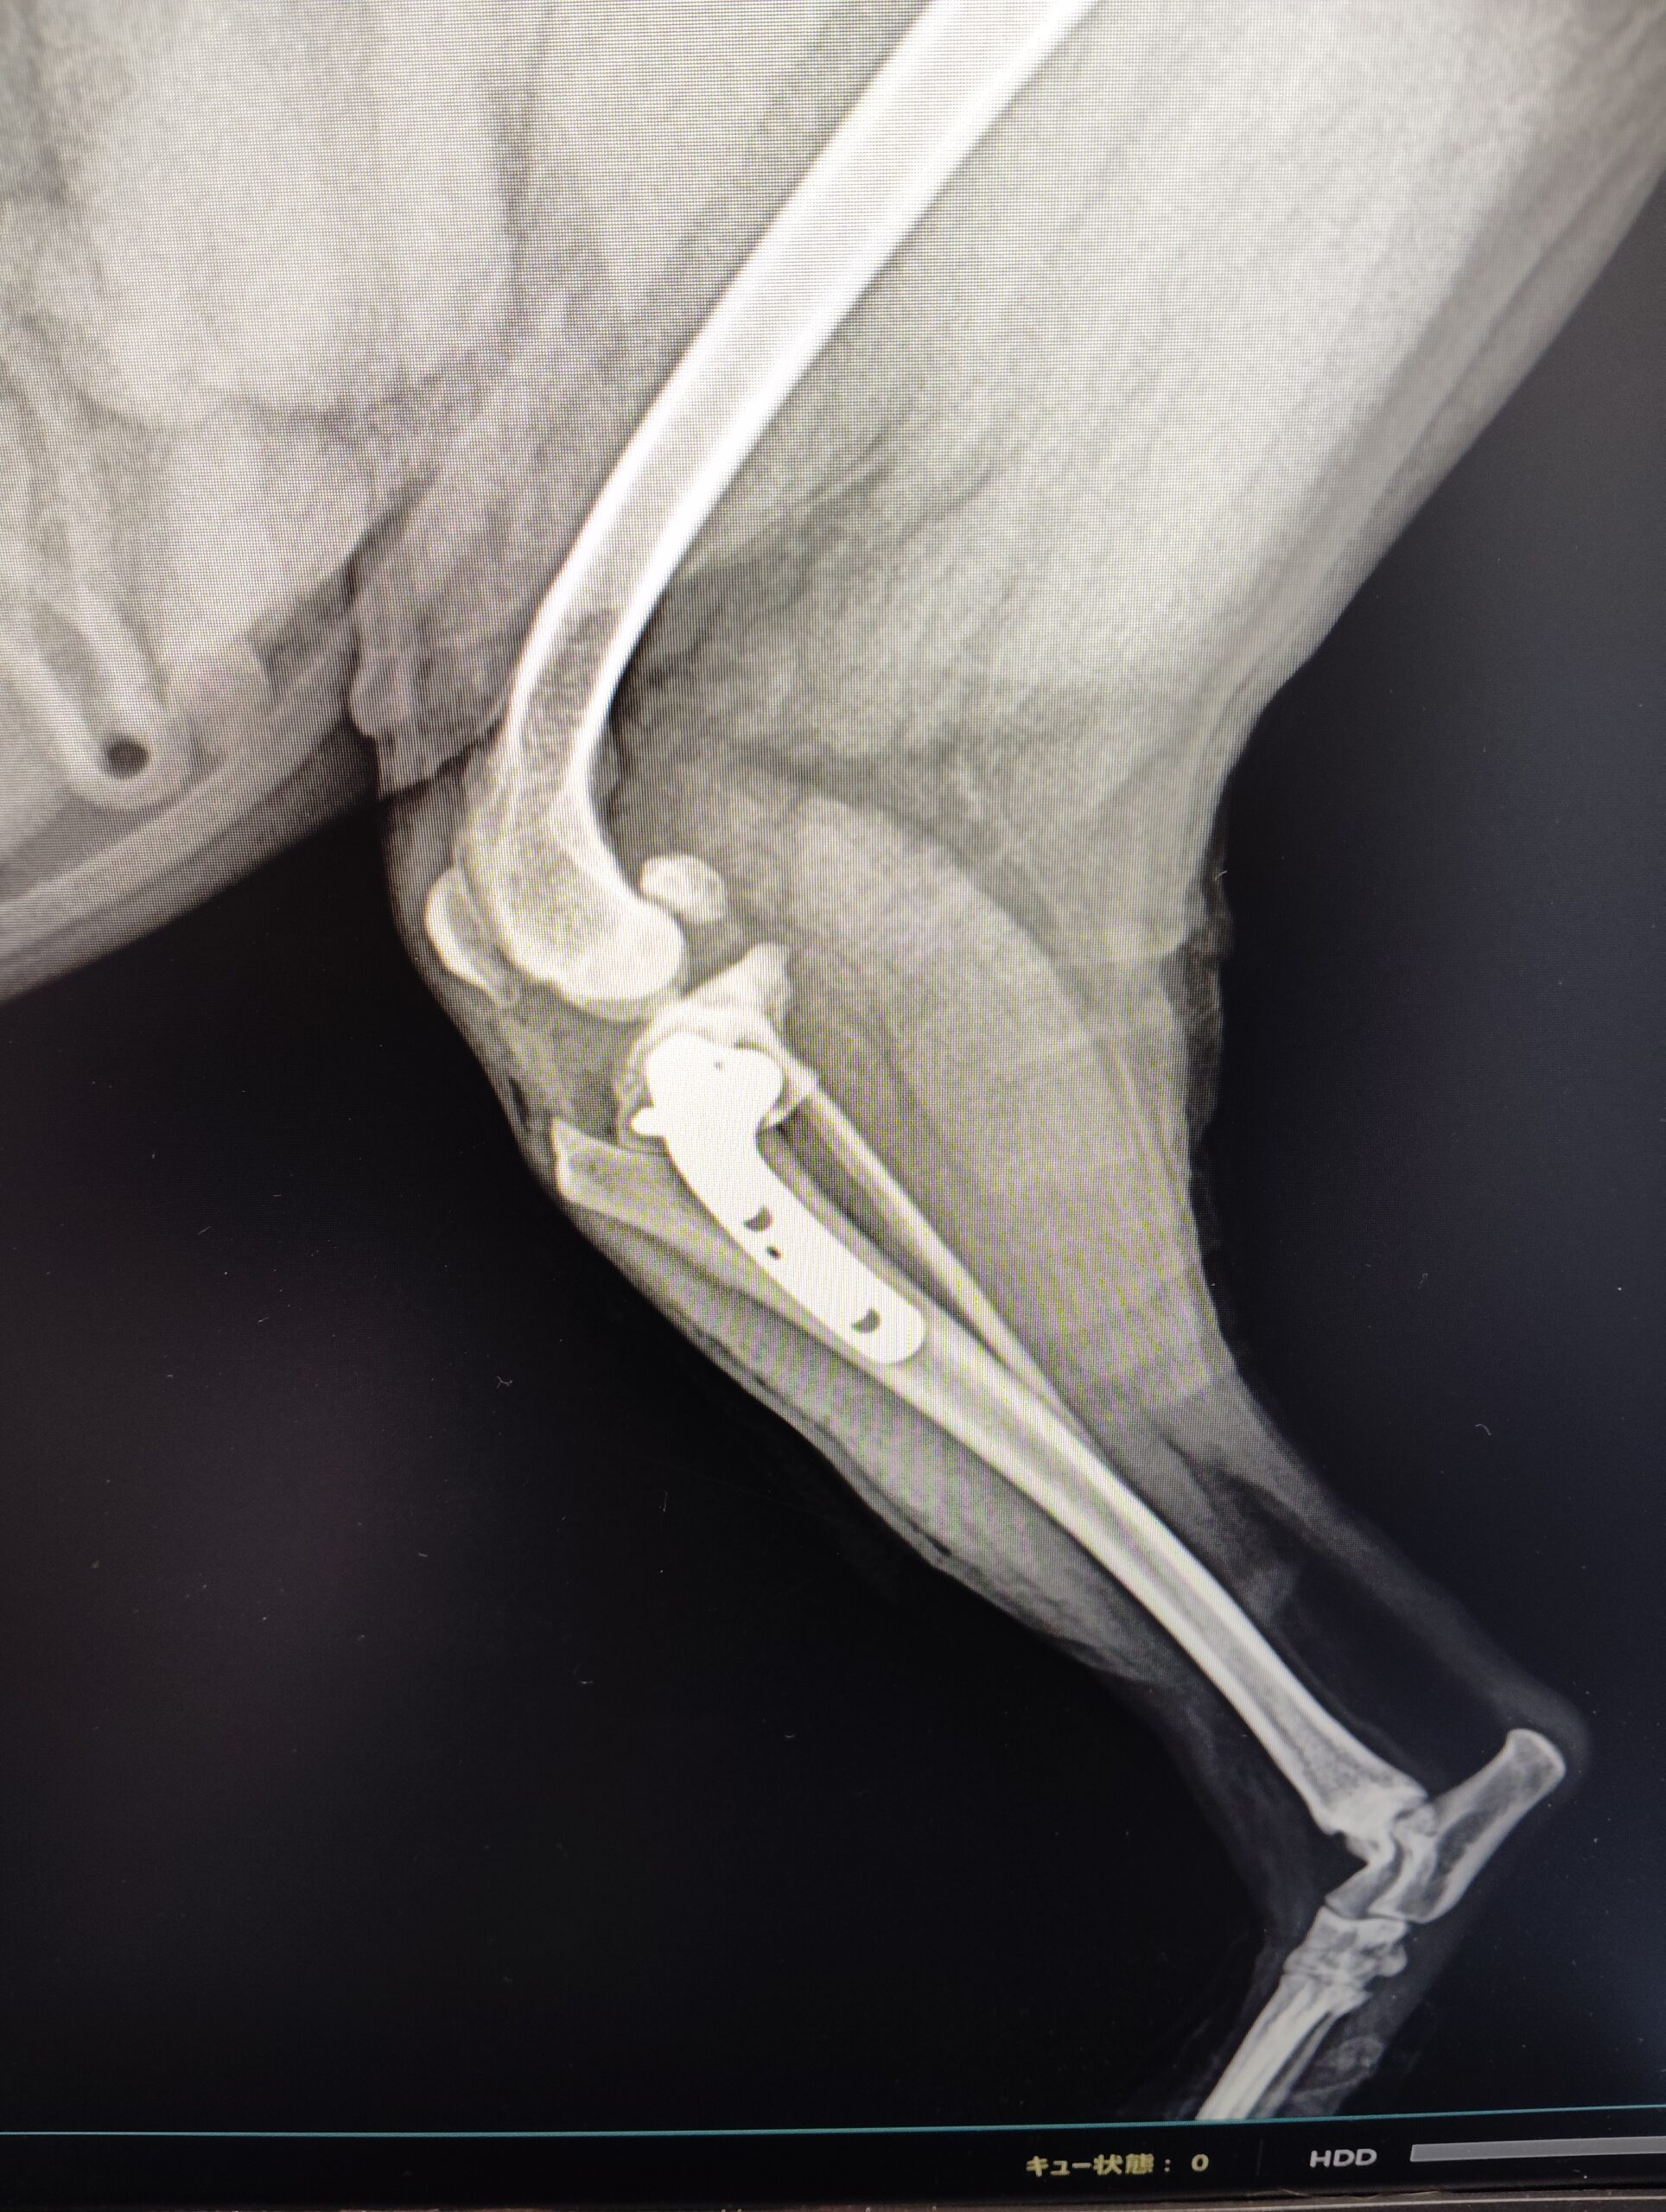

主な疾患

骨折全般、前十字靭帯断裂、膝蓋骨脱臼、LCPD病(レッグ・カルベ・ペルテス病)、股関節脱臼、仙腸関節脱臼、肩関節脱臼、肘関節形成不全、肘関節脱臼、

股関節形成不全、癒合不全、変形癒合、 皮膚腫瘍切除